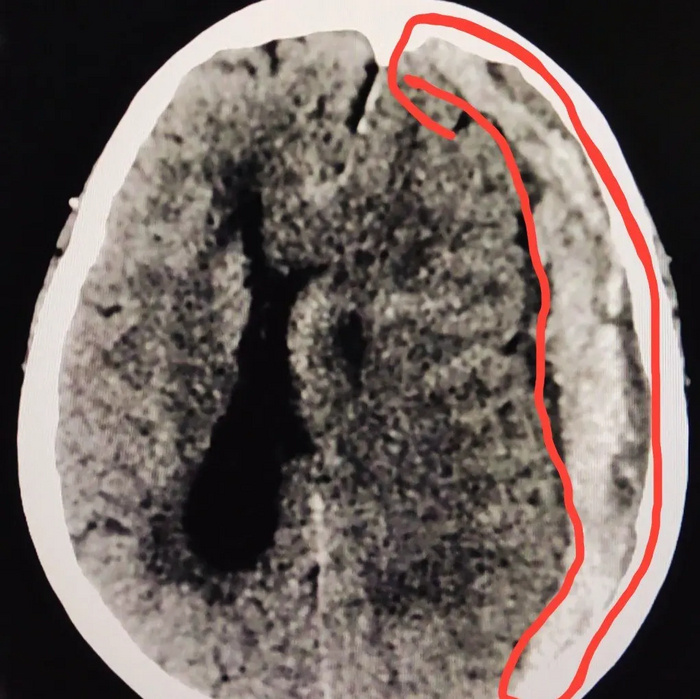

На КТ головного мозга субдуральная гематома слева (на картинке она справа, обведена красным цветом)

Со смещением срединных структур мозга (обозначено красной линией)